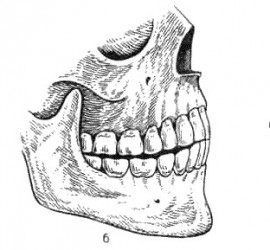

Аппарат представляет собой проволочный нёбный бюгель, который используется для стабилизации положения моляров, после лечения дистализирующими аппаратами, а так же для предотвращения потери места при лечении с удалением зубов. Жёсткая фиксация кнопки Нансе с кольцами создает прочную конструкцию для удержания достигнутого результата лечения.